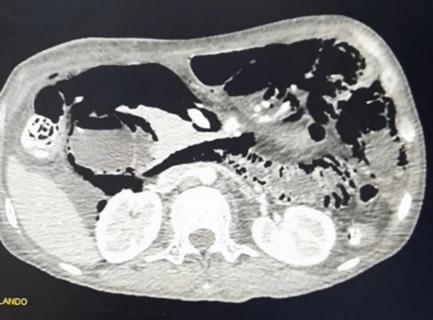

Pneumatosis intestinal por Enteritis lúpica, manifestación poco frecuente de lupus eritematoso sistémico

Intestinal pneumatosis due to lupus enteritis, a rare manifestation of systemic lupus erythematosus

Alejandra Vargas, Juan Candia................................................................................................................81-87